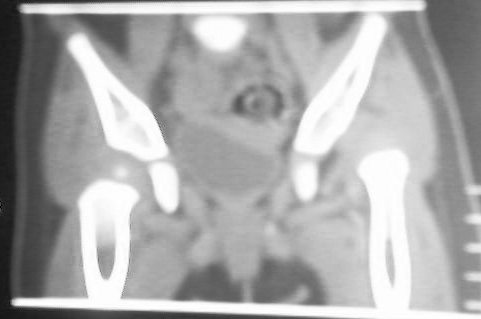

标题: PED0514双胞胎,1岁10个月,走路不稳。

老二:

先天性左侧髋关节脱位。

应该是典型的先髋。蛙式复位就可以了,何必ct呢。

左侧先天性髋关节脱位.典型!